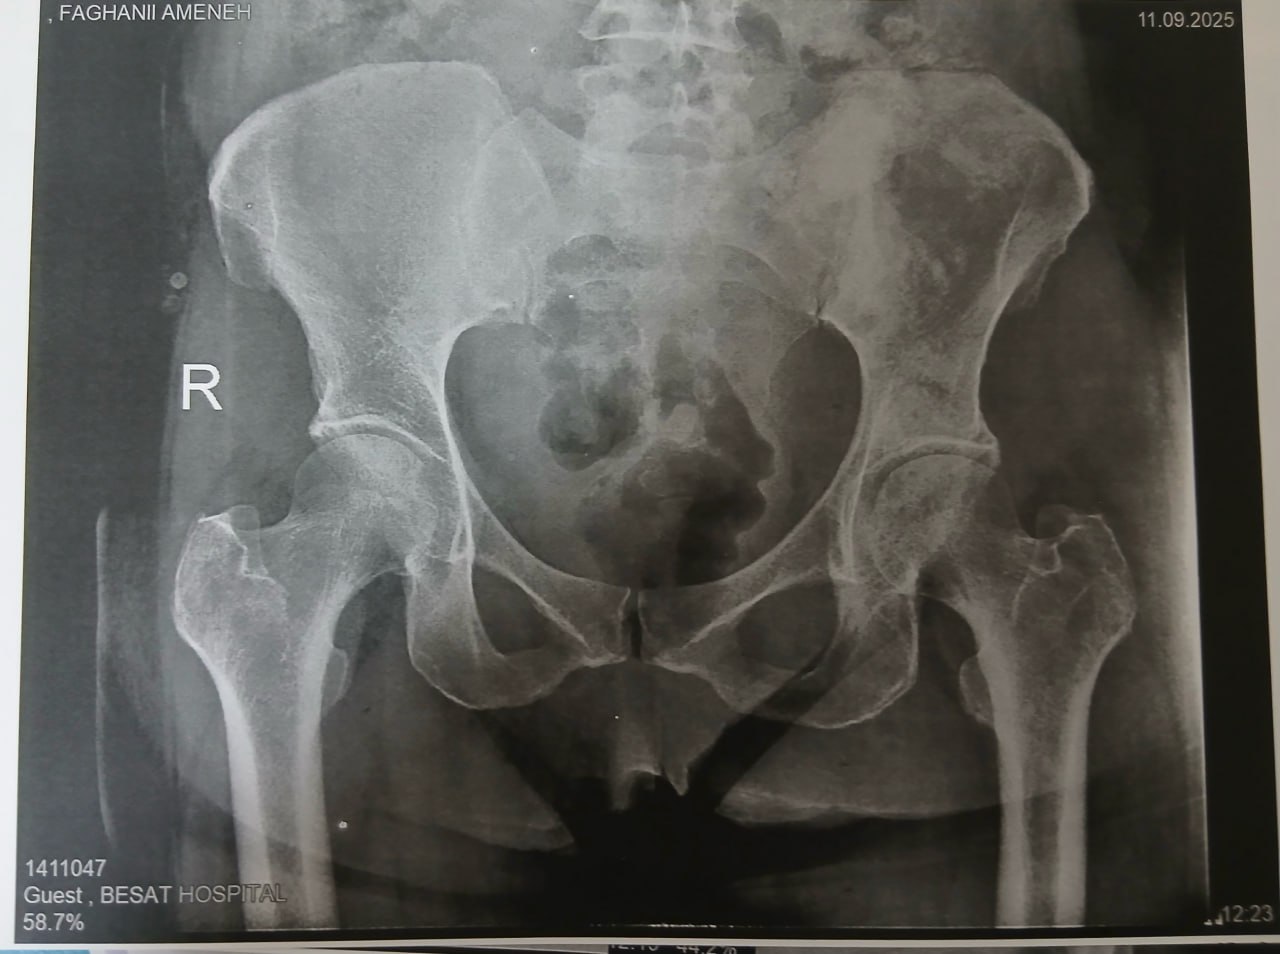

(تصویر مربوط به این مراجعه نیست) Other:

(تصویر مربوط به این مراجعه نیست) Other:

(تصویر مربوط به این مراجعه نیست) Other:

(تصویر مربوط به این مراجعه نیست) Other: